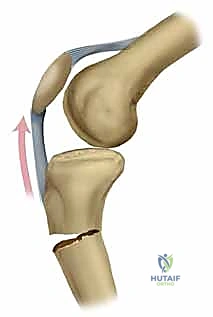

ولكن مع التطور المذهل في الطب الحديث والهندسة الطبية الحيوية، برز التسمير النخاعي (Intramedullary Nailing) كالمعيار الذهبي (Gold Standard) لعلاج الأغلبية العظمى من كسور الساق. تعتمد هذه التقنية المتقدمة على إدخال مسمار معدني مجوف ومصمم هندسيًا ليتطابق تماماً مع الانحناءات الطبيعية للعظم.

التسمير النخاعي ليس مجرد عملية جراحية، بل هو تطبيق عملي لمبادئ الميكانيكا الحيوية (Biomechanics) داخل جسم الإنسان. الفكرة تعتمد على وضع دعامة صلبة في "المركز الميكانيكي" للعظم (وهو التجويف النخاعي الأوسط).

- تقسيم الأحمال (Load-Sharing): المسمار النخاعي يشارك العظم في تحمل وزن الجسم، على عكس الشرائح التي تتحمل الوزن بالكامل (Load-Bearing) مما قد يؤدي لكسر الشريحة نفسها أو ضعف العظم لاحقاً.

- التثبيت التشابكي (Interlocking): يتم تمرير مسامير صغيرة عرضية عبر العظم والمسمار النخاعي في الطرفين العلوي والسفلي، مما يمنع دوران العظم حول المسمار ويحافظ على طول الساق الطبيعي بدقة متناهية.